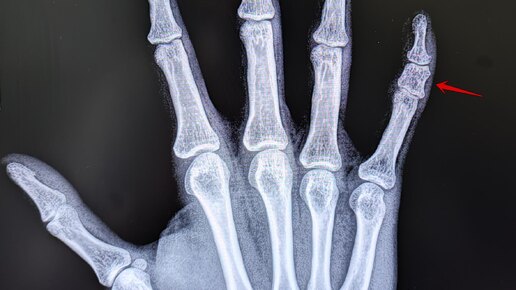

Брахидактилия

Это врождённая аномалия развития, характеризующаяся укорочением пальцев кистей и/или стоп из-за недоразвития или отсутствия фаланг. На Р-граммах правой кисти в 2х проекциях: травматических, деструктивных изменений не выявлено. Структура костной ткани не изменена. Средняя фаланга пятого пальца укорочена, утолщена. По остальным отделам кисти-без явной костной патологии. Заключение: Врожденная...